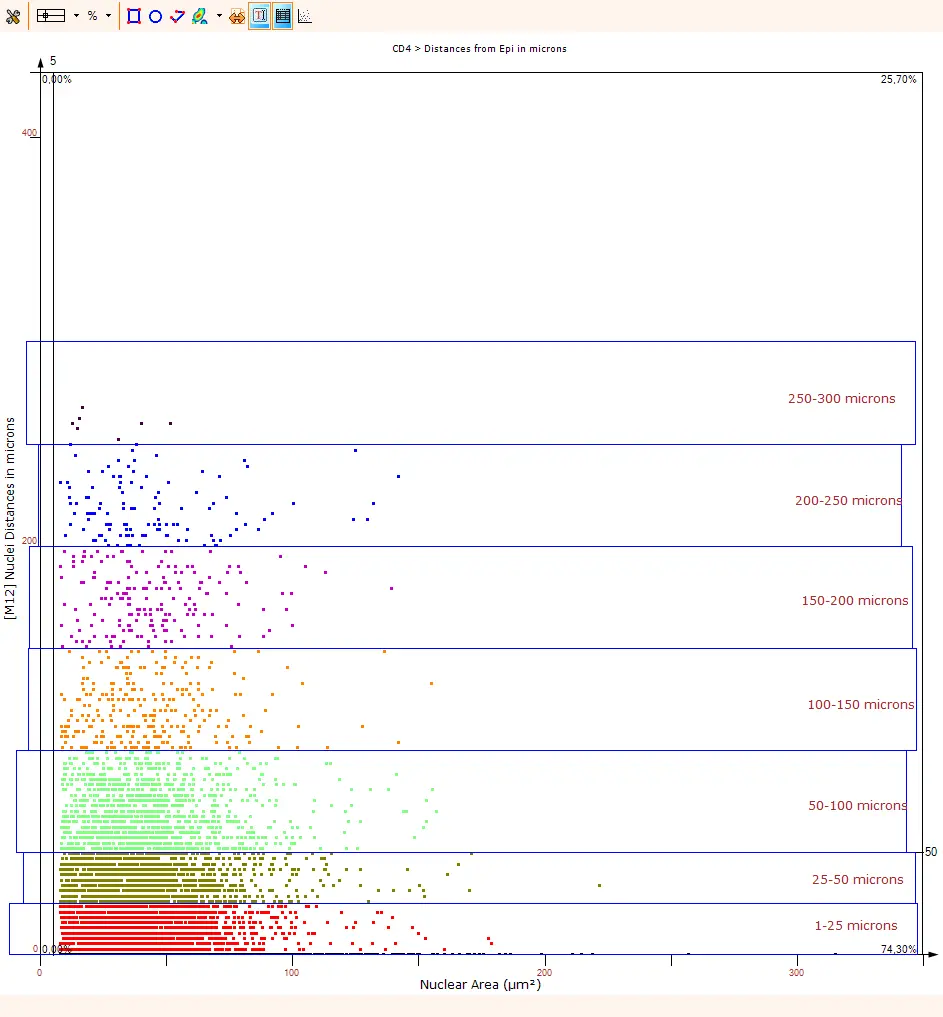

SynNotch-CAR T Cells as Promising Therapy for Solid Tumors

Choe et al. (UCSF) report in Science Translational Medicine on SynNotch-CAR T cells in a glioblastoma PDX model. In-situ T cell dynamics were imaged with TissueFAXS and quantified via StrataQuest.